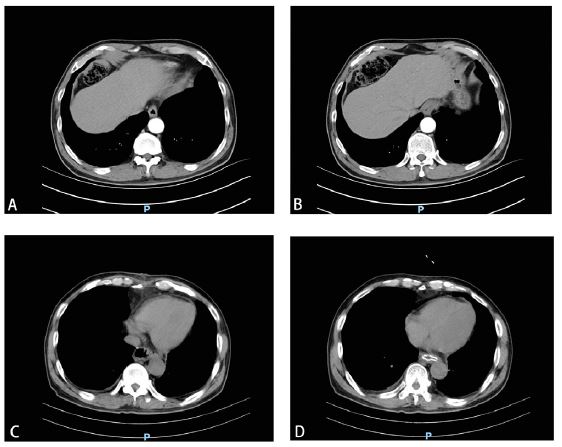

Ten months postoperatively, the patient presented to the emergency department on January 25, 2024, with “abdominal pain for 2 days, worsening for half a day,” characterized by continuous dull pain in the upper abdomen, alleviated when sitting or bending forward and severe when lying flat. He denied any history of vomiting or respiratory difficulty. Physical examination showed normal vital signs, severe tenderness in the right upper and upper abdomen, and normal bowel sounds. Initial laboratory results, including cardiac enzymes and electrocardiogram, showed no abnormalities. A thoracoabdominal CT scan indicated the esophagojejunostomy and dilated jejunal loops herniated through the hiatal hernia into the right hemithorax, forming a right-sided hiatal hernia (Figures 2A & 2B). There was no free fluid or air in the thoracic cavity.

Figure 2: Thoracoabdominal CT scan showing partial herniation of the small intestine into the right thoracic cavity, compressing the right lung.

A. Transverse view. B. Sagittal view.